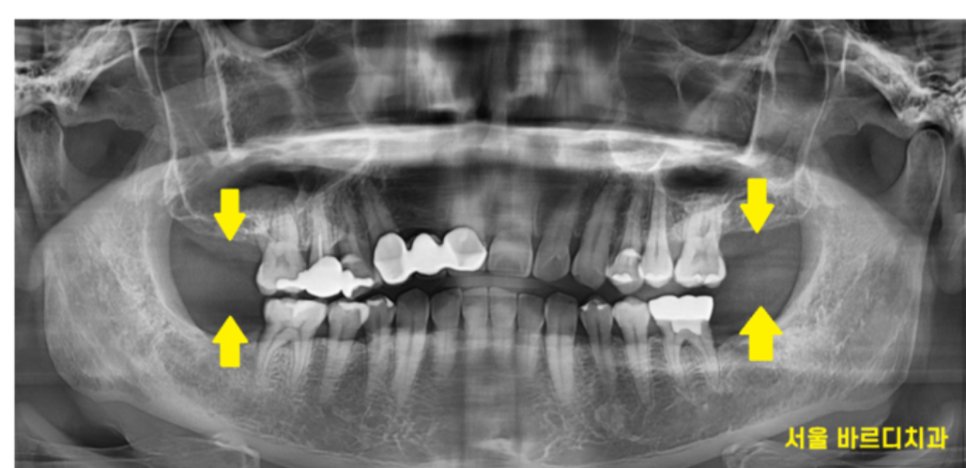

양쪽 맨 끝 어금니가 위아래로 발치된 환자분입니다.

한쪽도 아니고 양쪽으로 위아래 모두

끝에 치아만 발치하셨으니